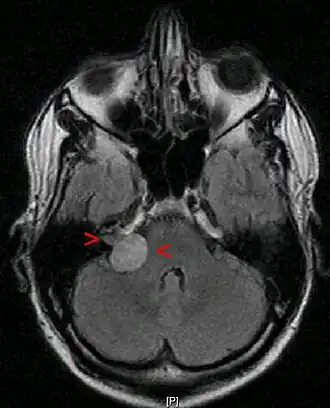

Методом выбора при диагностике является магнитно-резонансная томография.